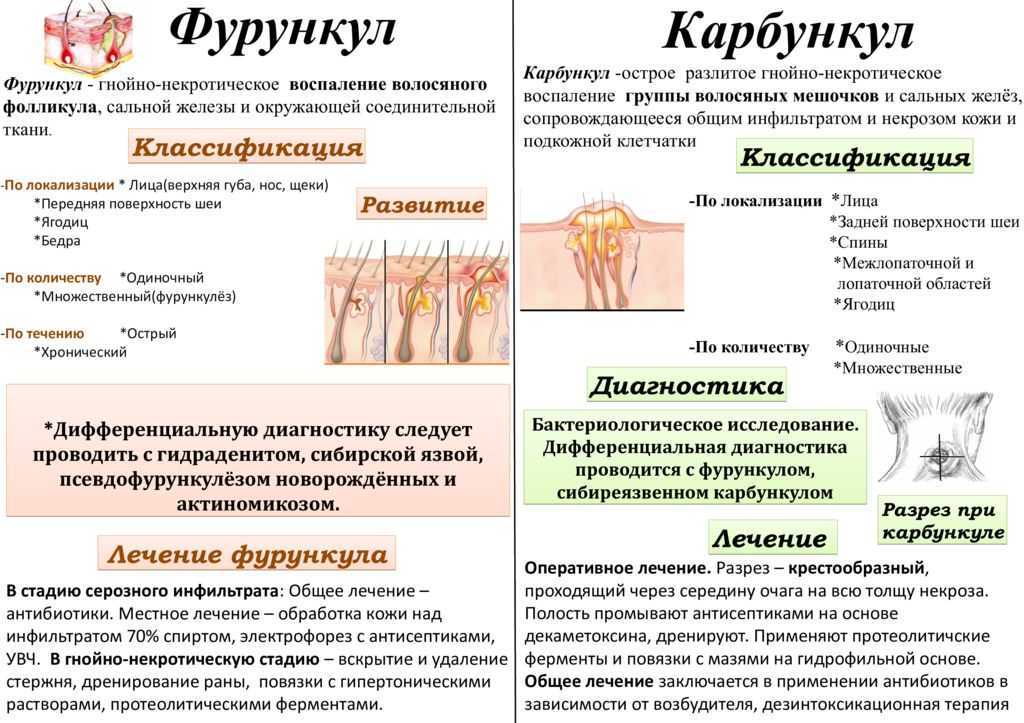

Код мкб 10 атерома головы

Код мкб 10 атерома головы 109 фото